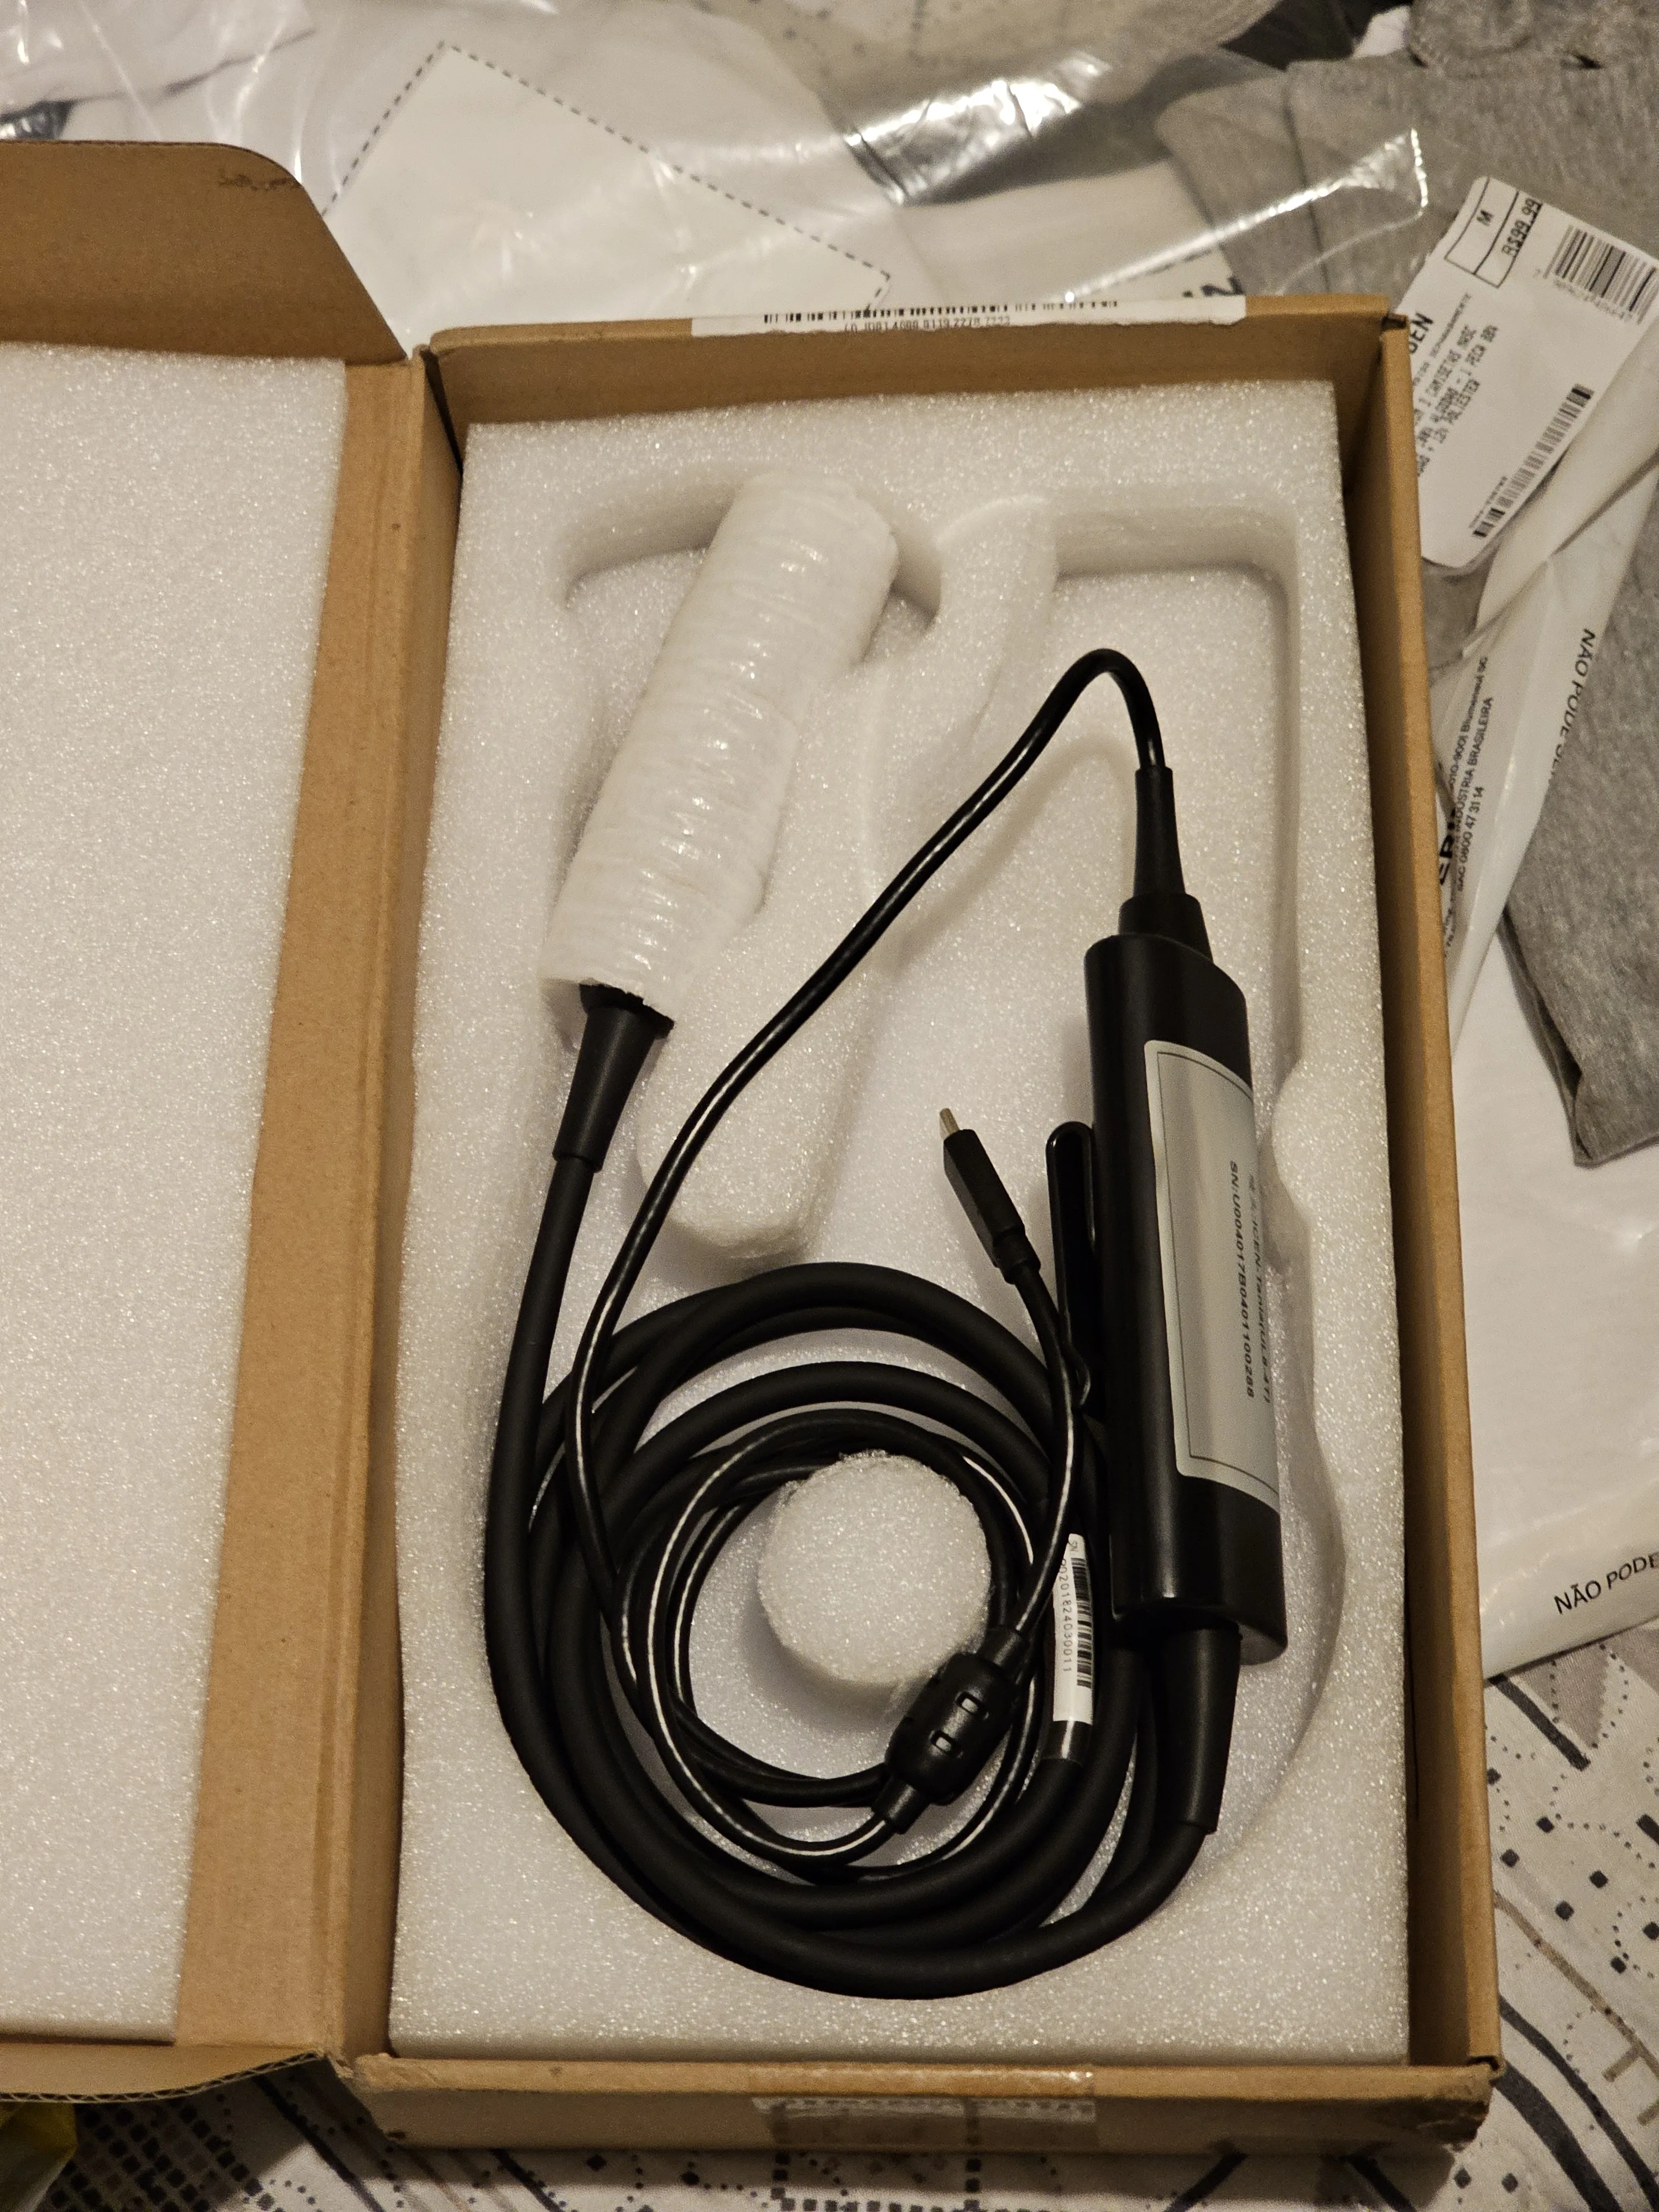

00:23#Sonoscape Ultrasound Scanner

00:04Ultrasound Scanner mindray

01:49Color Doppler Machine

00:44Color Doppler Machine

00:23#Sonoscape X3 ultrasound machine

02:22Color Doppler Machine

02:48Color Doppler Machine